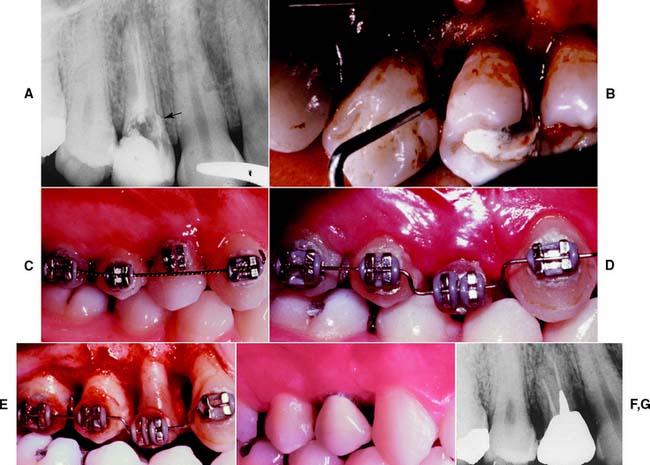

Orthodontic extrusion65,66,81 (Fig. 6-21) may be considered whenever a fracture or carious lesion extends apical to the free margin of the gingiva. However, it is especially important when esthetics is a prime concern. The margin of the fracture or lesion is moved away from the alveolar crest orthodontically (with brackets, wires, and/or elastic bands), and the gingiva often requires surgical repositioning when orthodontic therapy is completed.

Fig. 6-21 Orthodontic extrusion before restoring a badly damaged tooth. A, This maxillary first premolar has been perforated mesially (arrow). A surgical crown lengthening was contraindicated because of the level of the perforation apical to the osseous crest. B, A flap was reflected to débride the perforation and associated lesion. C, Orthodontic brackets cemented with rebounding wire initially. When the wire is placed in the premolar bracket, it imparts an occlusally directed force. (The occlusion must be relieved periodically as the tooth moves.) D, Completion of the extrusion. E, Osseous recontouring at this stage ensures a harmonious bony and gingival contour. F and G, Coronal tooth structure restored with a metal-ceramic crown.

(Courtesy of Dr. S. B. Ross.)